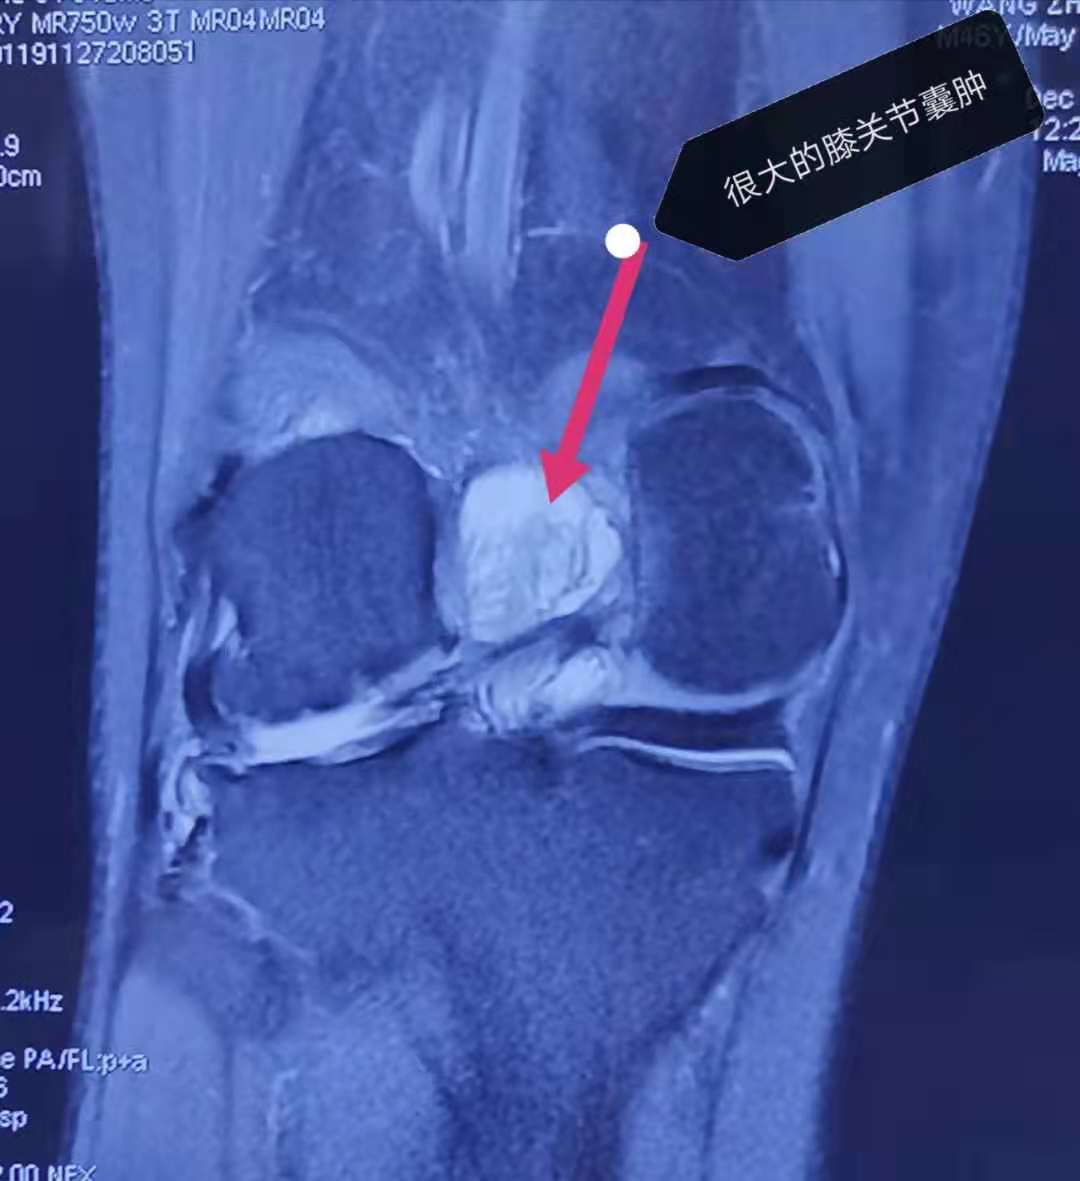

这次患友来医院做核磁检查,发现他的右膝外侧半月板已经完全撕裂了,我们把这种情况称为"桶柄样撕裂";同时还有严重的骨关节病,一个外侧间室的软骨已经磨损殆尽,关节缝已经消失了,将来甚至有可能需要做膝关节的置换。